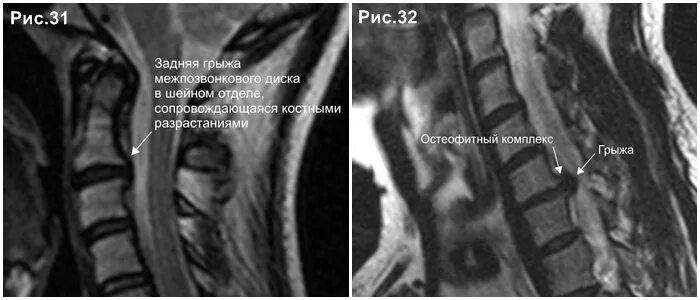

Каудальная миграция грыжи диска